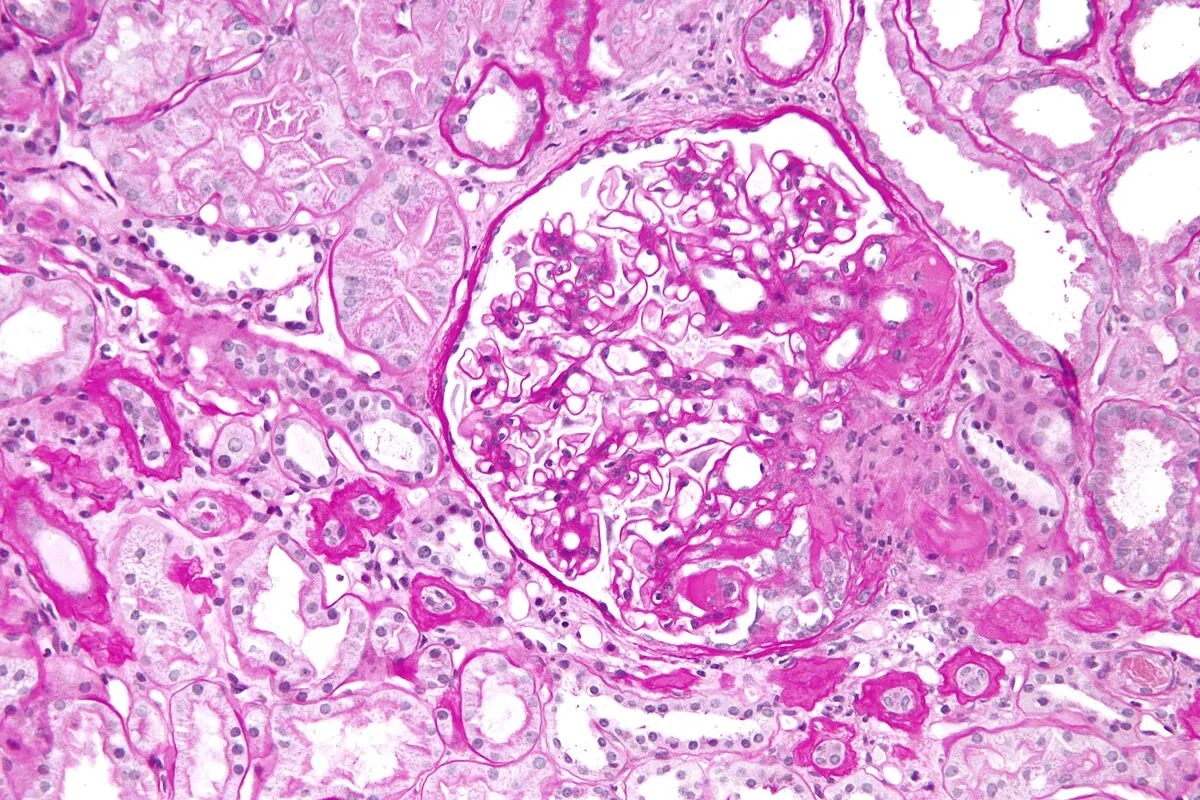

A alta da IRA realmente significa recuperação… ou apenas o começo da DRC futura? Albuminúria, reintrodução de IECA/BRA, iSGLT2 e seguimento precoce podem mudar completamente o prognóstico pós-IRA — e muita gente ainda foca só na creatinina da alta. Esse artigo do Clinical Kidney Journal traz 10 pontos práticos que todo nefrologista deveria revisar no seguimento pós-IRA.